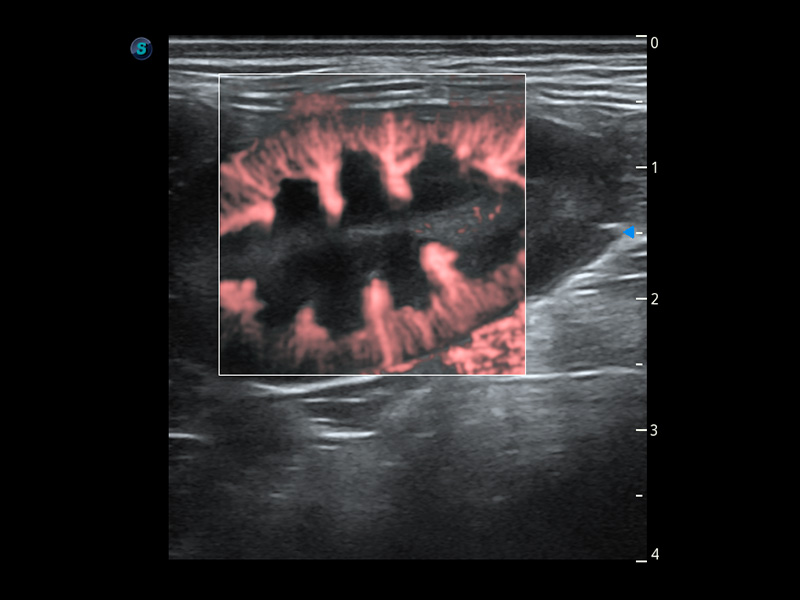

ProPet 60 作为一款高端台式动物超声设备,为动物医生的日常诊断提供了一系列贴合动物临床需求、解决临床实际问题的高级成像功能。凭借全系列高清探头,满足医生对腹部、心脏、生殖、浅表、肌骨等成像的所有需求,切实帮助您提升检查效率,提高诊断信心。

动物是人类最亲密的朋友和最值得信赖的伙伴。16877太阳集团也一直致力于探索动物专用的超声影像解决方案。 全新推出的ProPet系列,是16877太阳集团在动物超声影像智能化、专业化、精准化的一次跨越式革新。动物不能用言语来表述自己的不适,通过超声影像,ProPet系列搭建了动物医生与不同物种沟通的“桥梁”,为动物医生注入了“治愈之力”。